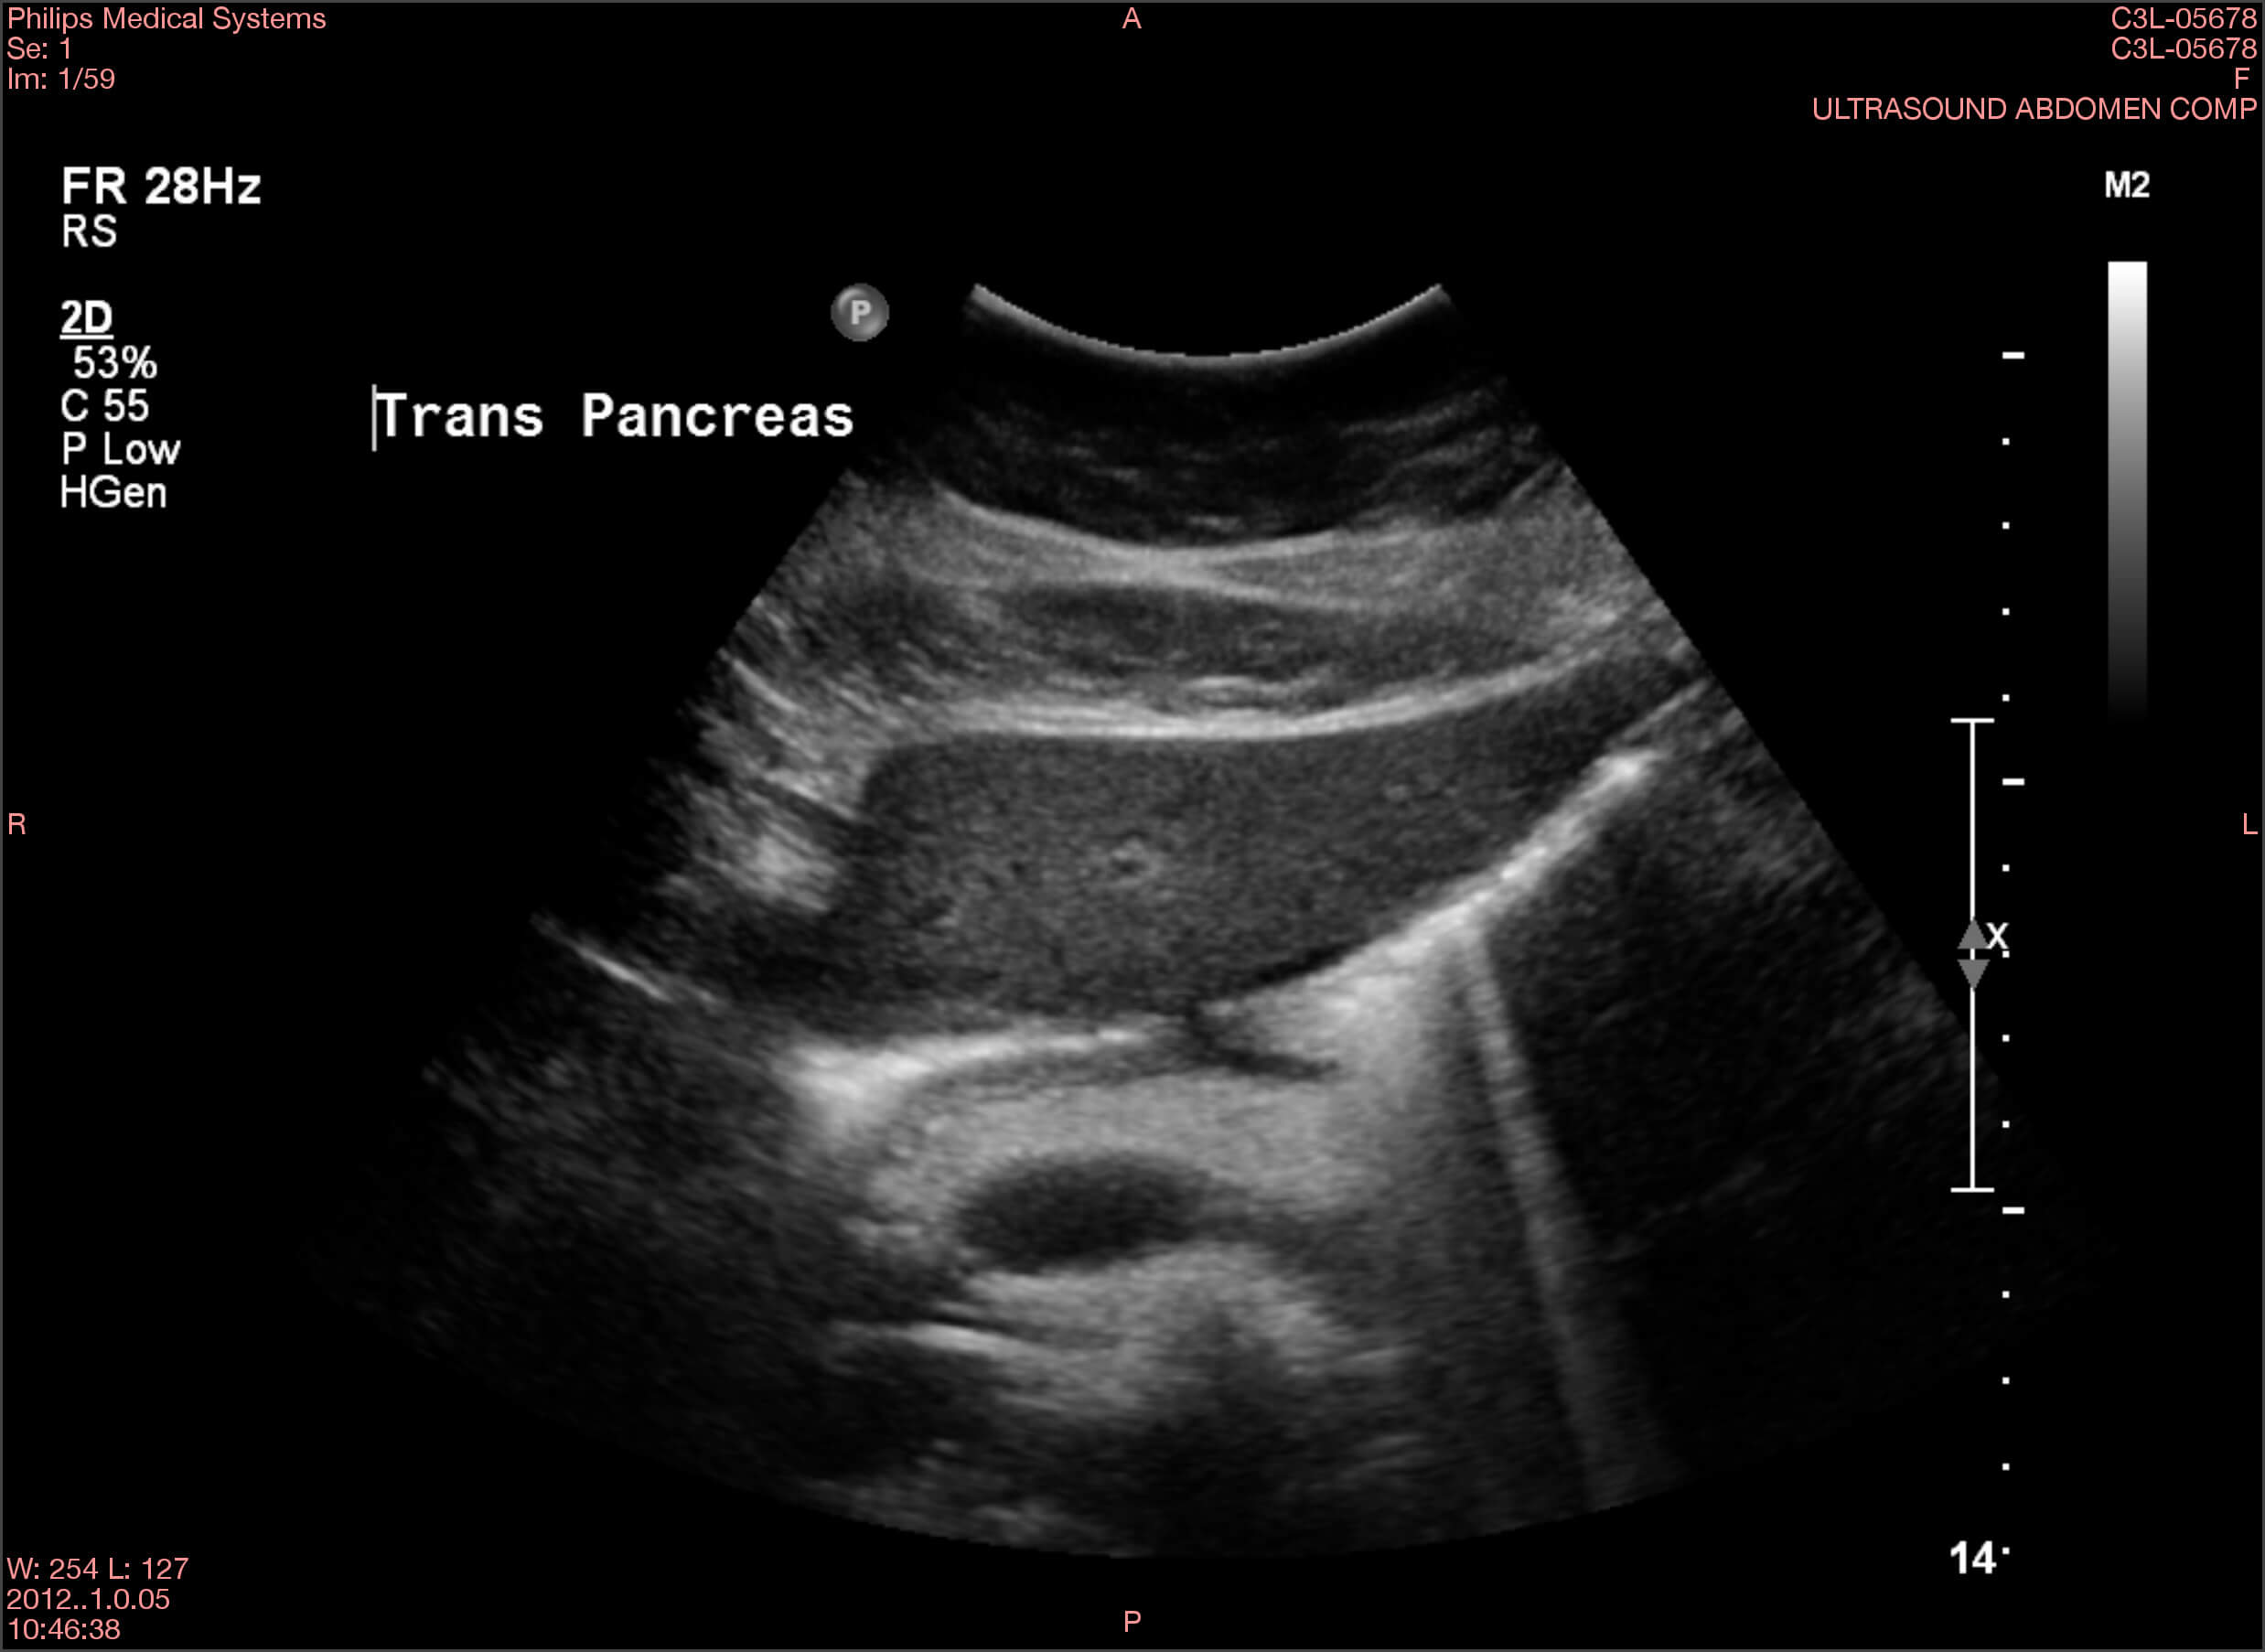

Die Ergebnisse der durchgeführten Untersuchungen kannst du dir hier anschauen:

Die Befunde geben eindeutige Hinweise auf die Erkrankung von Frau Lorenz. Wie bewertest du die Ergebnisse?